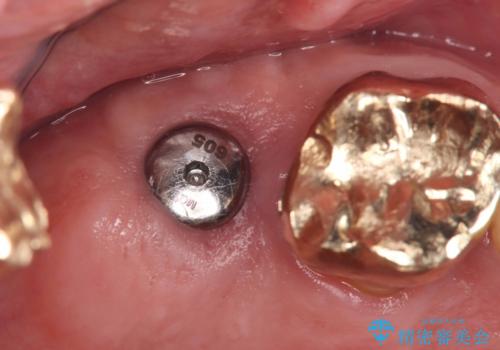

抜歯即時埋入の適応と判断し、抜歯当日にインプラント埋入を行う「抜歯即時埋入」にて処置を実施しました。

抜歯即時インプラントの利点(共振周波数解析を用いたISQ値の測定により、客観的かつ数値でインプラントの安定性を評価できるようになったため、予知性が高く安全な治療となった。)

●低侵襲

抜歯窩を利用してインプラントを埋入するので、歯茎を切る必要が無く術後の痛みが出にくい